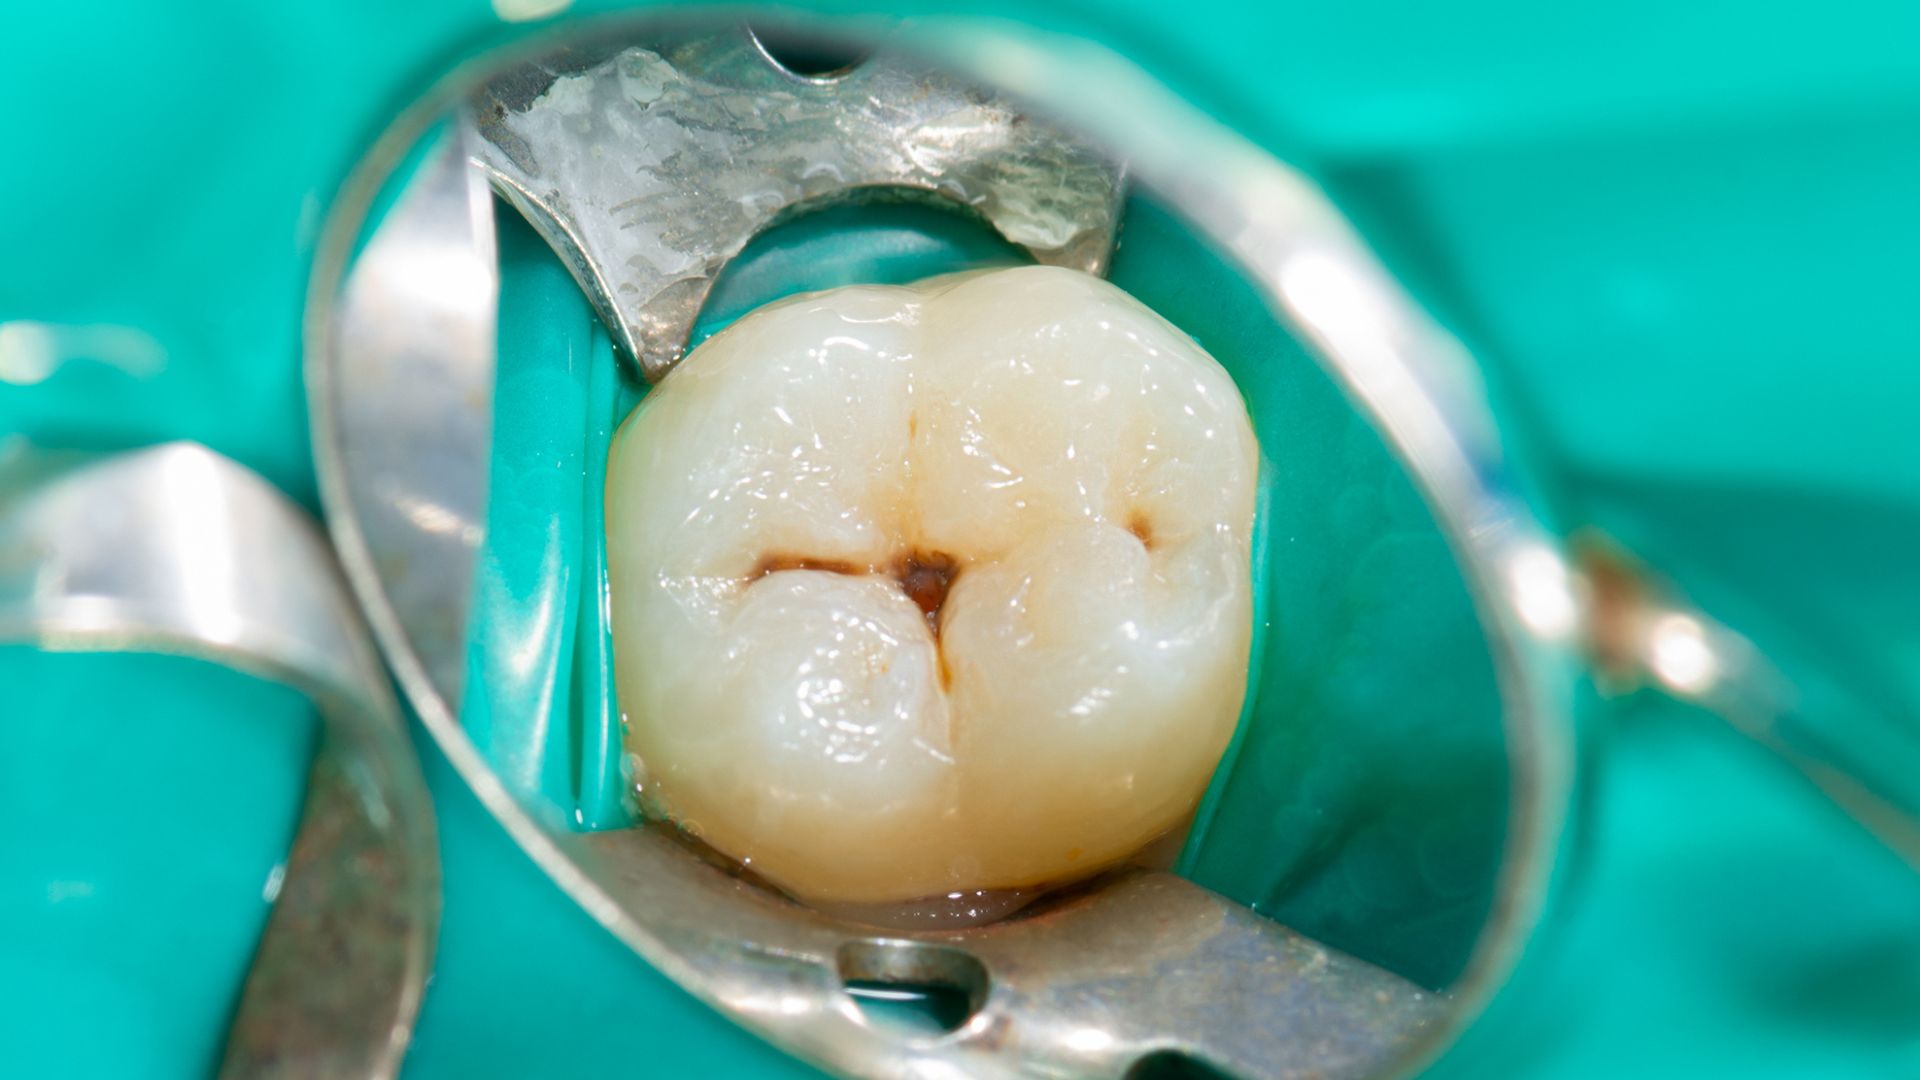

Se osservi la superficie masticante di un dente molare, noterai che non è liscia. È attraversata da piccoli solchi, fessure e fossette che aiutano a triturare il cibo.

Questi solchi, purtroppo, sono anche il punto debole del dente.

La loro forma profonda e stretta li rende estremamente difficili da pulire con lo spazzolino.

Le setole spesso non riescono a raggiungere il fondo, dove placca e batteri trovano un ambiente ideale per annidarsi e dare inizio al processo di carie.